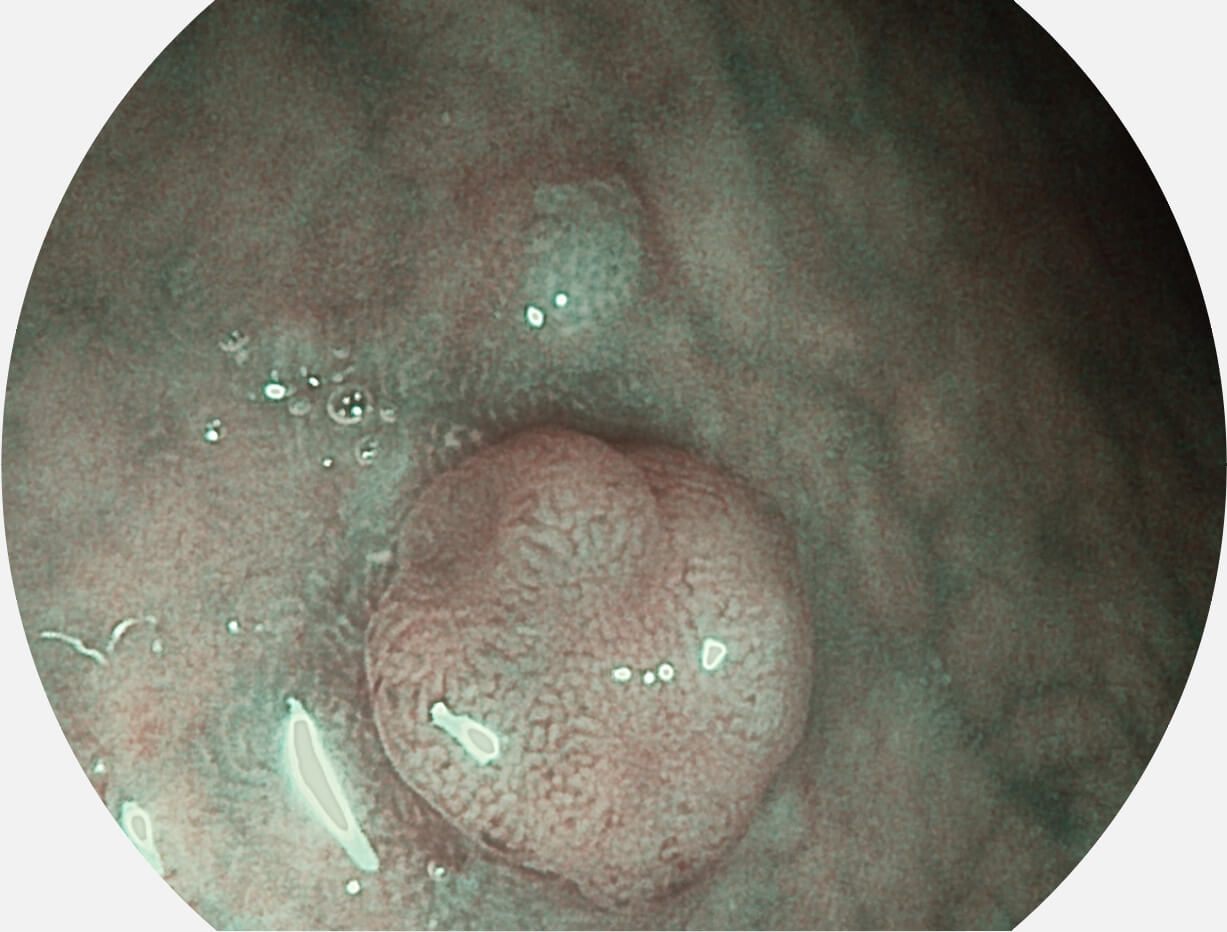

Spectral Focused lmaging, SFI

图像具有高亮度、高黏膜血管颜色对比度的特点,且不改变粘液、食物残渣、粪便的基本颜色,可在中远景下进行观察,助力消化道早期疾病的诊断。

白光图像

SFI图像

采用光路合束技术,光谱自由度高,实现了更丰富的照明模式,染色模式SFI及VIST,从远景到近景,助力消化道早期疾病诊断。